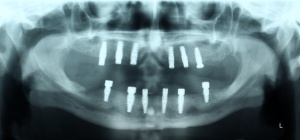

Zum Ausgleich der konsekutiv vorliegenden Weichgewebsatrophie erfolgte im Juni 2012 nach Genehmigung des Antrags durch das Sanitätsamt der Bundeswehr zunächst die Implantation von 2 Weichgewebsexpandern (Firma Osmed) im Oberkiefer (Abb. 10). Nach Schaffung eines adäquaten Weichgewebsbettes wurde im Juli 2012 zur Korrektur der extremen Hartgewebsatrophie eine Augmentation vom Beckenkamm durchgeführt (Abb. 11). Im Dezember 2012 erfolgten in Lokalanästhesie nach ungestörter Einheilung die Materialentfernung der Osteosyntheseschrauben und die Implantation von 4 dentalen Implantaten (Firma Nobel Biocare, Replace straight, Abb. 12). Durch Atrophie und die rekonstruktiven Operationen bedingt, wurde zur Korrektur der ungenügenden Weichgewebsverhältnisse eine Vestibulumplastik nach 3 Monaten mit Einlagerung einer bioresorbierbaren Membran (Firma Botiss, Mucoderm) durchgeführt. Nach weiteren 3 Monaten erfolgte die Freilegung der Implantate (Abb. 13) mit einer Rolllappenplastik an jedem Implantat zur vestibulären Rekonturierung der Schleimhaut.